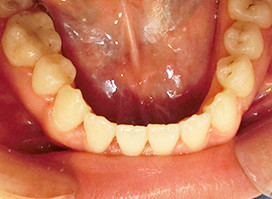

口元症例③

- 性別:男性

- 年齢: 33歳

- 治療期間:1年10ヵ月

- 治療内容:第1小臼歯(4番目の歯)を4本抜歯し、マルチブラケット装置で矯正することで上の出っ歯、下の前歯のデコボコが改善されました。

最も気にされていたお口元の突出感もなくなり、美しい『E-line』なりました。 - 費用:892,500円(税込)

- リスク・副作用:治療後の後戻り・歯根吸収・歯髄壊死・歯肉退縮が生じる場合がございます。